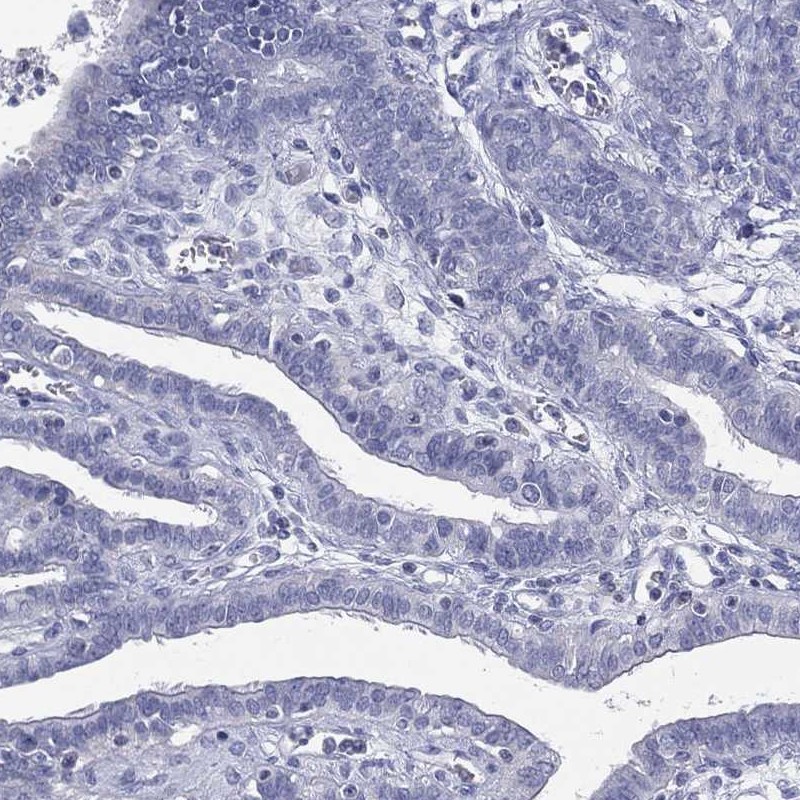

Immunohistochemistry analysis in human heart muscle and fallopian tube tissues using Anti-CPT1B antibody. Corresponding CPT1B RNA-seq data are presented for the same tissues.